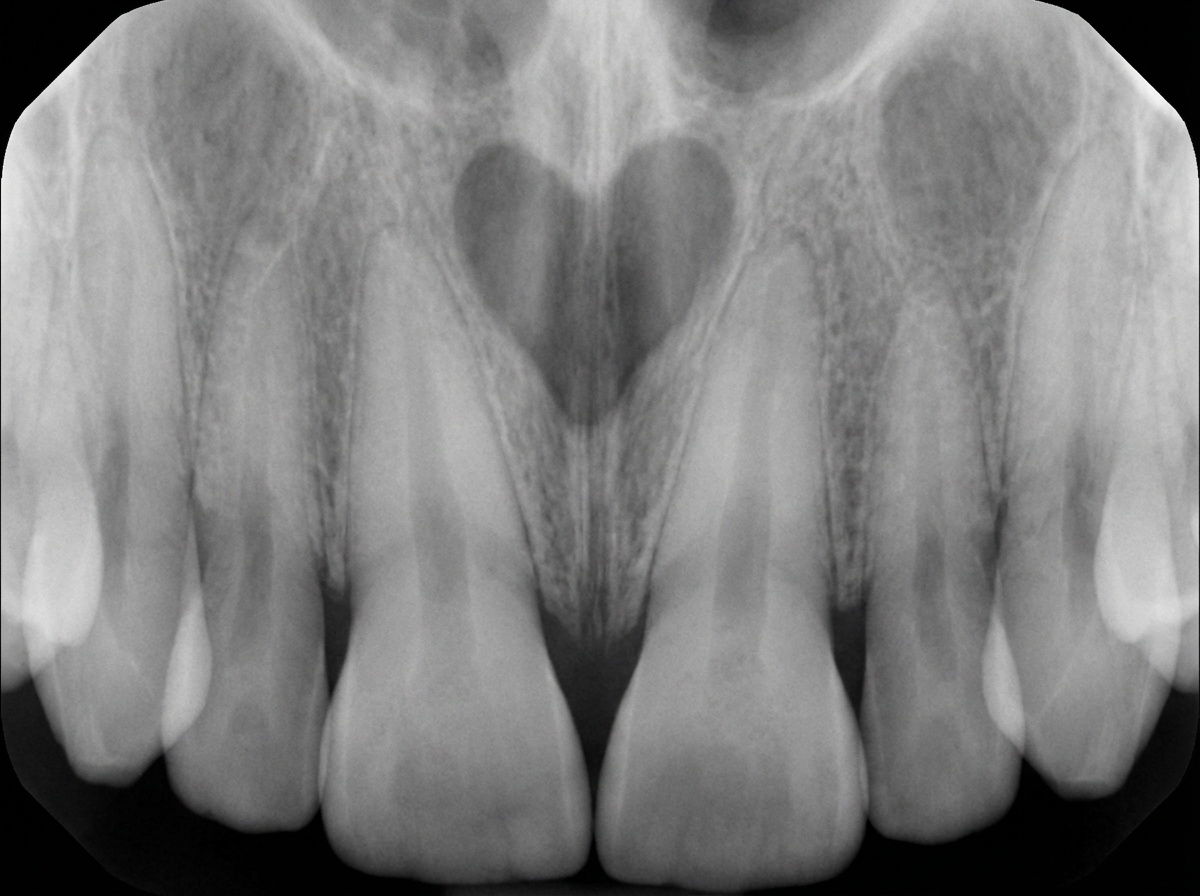

Which of the following statements is FALSE regarding the phenomenon illustrated below?

Explanation: ***None of the above.*** - All three statements (A, B, C) accurately describe **cervical burnout**, a normal radiographic phenomenon seen at the **cementoenamel junction (CEJ)**. - Since the question asks which statement is FALSE and all given statements are TRUE, "None of the above" is the correct answer. *The gap between the cementoenamel junction (CEJ) and the alveolar bone crest contains dentin only, leading to less material in the cervical region to absorb X-rays.* - This statement is TRUE - the absence of **enamel** in this region leaves only **dentin**, which is less radiopaque. - The reduced **radiopacity** creates the characteristic **radiolucent bands** seen in cervical burnout. *The rounded cross-section of most roots accentuates this phenomenon peripherally.* - This statement is TRUE - the **curved anatomy** of root surfaces causes more pronounced burnout at the **mesial and distal aspects**. - The **cylindrical shape** of roots creates varying tissue thickness, enhancing the radiolucent appearance peripherally. *The mesial and distal surfaces of teeth show bands of burnout, which end abruptly at the alveolar bone margin.* - This statement is TRUE - **cervical burnout** appears as **bilateral radiolucent bands** on the mesial and distal root surfaces. - These bands have a characteristic **sharp demarcation** at the level of the **alveolar bone crest**, distinguishing them from pathological lesions.